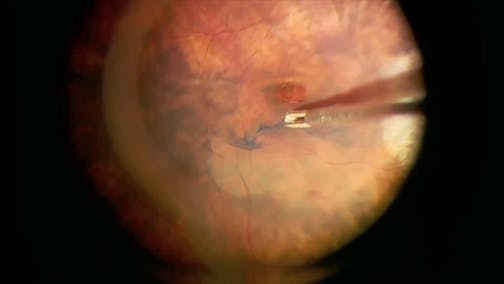

Optic Nerve Pit

Kourous A. Rezaei, MD